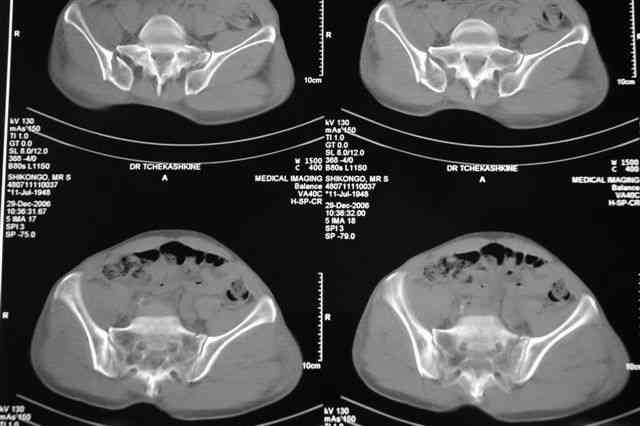

Я помню технику транссакральной фиксации тазового кольца длинными 5 мм Шанцами - повреждения типа В, в этом же случае задний отдел тоже вовлечен

т.е комбинированная нестабильность, поэтому вопрос - достаточно ли только двух Шанцев для стабилизации таза? Что вы думаете об anterior Right SI joint plating + tension band plating from the back.?

Элегантная фиксация, поздравляю.Но ваш случай : одноплоскостная горизонтальная нестабильность Tyle B2.2 отличен от представленного мной - у

моего больного + вертикальная нестабильность за счет повреждения правого крестцово-подвздошного сочленения и перелома заднего отдела подвздошной

кости- С2 тип. Поэтому и возникла дилемма : выбор оптимальной фиксации заднего отдела:

По-поводу фиксации таза спонгиозными винтами. Данный способ все-таки показан для фиксации повреждения крестцово-подвздошного сочленения или переломов крестца. Мне кажется, что в данной случае ситуация иная - имеется перелом "основания" крыла подвздошной кости (в который вовлечена и поверхность, составляющая крестцово-подвздошное сочленение). Не уверен, что фиксация данного повреждения (и заднего полукольца) винтами будет стабильной, так как именно на уровне 1-2 крестцовых позвонков (где обычно вводят винты) линия перелома уходит в латеральном направлении от крестцово-подвздошного сочленения.

Я просмотрел томограммы и у меня создалось впечатление, что винтам есть за что *зацепиться*. В сочетании с 5 мм Шанц винтами, проведенными через нижне-переднюю ость спереди назад через КП сочленения -стабильность тазового кольца должна восстановиться. - Это , конечно, при условии , что закрытая рнепозиция будет успешной.

Травма произошла 22 или 23 декабря, ко мне больной попал 26 декабря, 3 января -остеосинтез перелома бедра и внутр.лодыжки.

после КТ отказался от этой идеи - двусторонний перелом крестца в зоне 1 - алярная часть, при попытке низведения правого гемипелвиса теоретически есть вероятность смещения

фрагмента крестца слева.